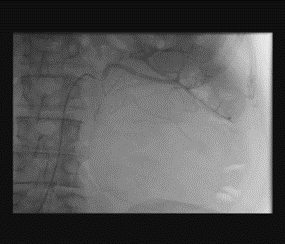

Renal artery embolization was performed under local anesthesia using the Seldinger technique, with complete occlusion confirmed angiographically (Figures 3-4). Six days later, a transabdominal left radical nephrectomy was performed. Intraoperatively, the kidney appeared markedly enlarged and deformed, containing cystic and soft-tissue components but without invasion of adjacent structures (Figures 5-6). The operation was uneventful, with minimal blood loss (approximately 300 mL) and no transfusion requirement. The postoperative course was smooth, and the patient was discharged on postoperative day five in good condition. Histopathological examination revealed that the upper pole lesion corresponded to a low-grade clear cell RCC with focal necrosis (Figures 7-8). The larger lesion was identified as a well-differentiated liposarcoma (Figures 9-10), correcting the initial radiologic misdiagnosis of angiomyolipoma. At the three-month follow-up, the patient remained asymptomatic. Laboratory results indicated mild renal impairment (creatinine 169 µmol/L, urea 9.2 mmol/L) but normal inflammatory markers. Ultrasonography revealed no recurrence or lymphadenopathy. Nephrology follow-up was continued due to reduced renal function. Six months postoperatively, CT imaging of the thorax, abdomen, and pelvis demonstrated no evidence of local recurrence or distant metastasis. Given the absence of standardized surveillance protocols for synchronous RCC and WDLPS, followup was conducted in accordance with conventional RCC and retroperitoneal sarcoma guidelines.

Figure 3: Angiographic visualization of arterial vascularization of the left kidney before embolization.